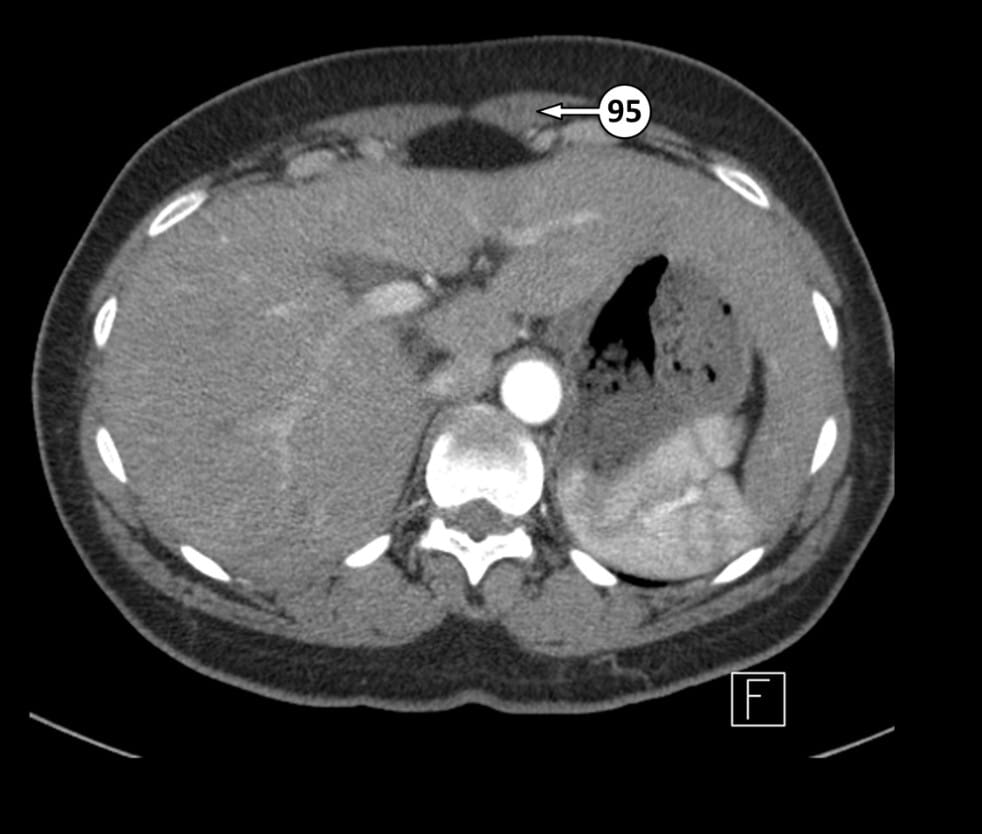

95. rectus abdominis muscle